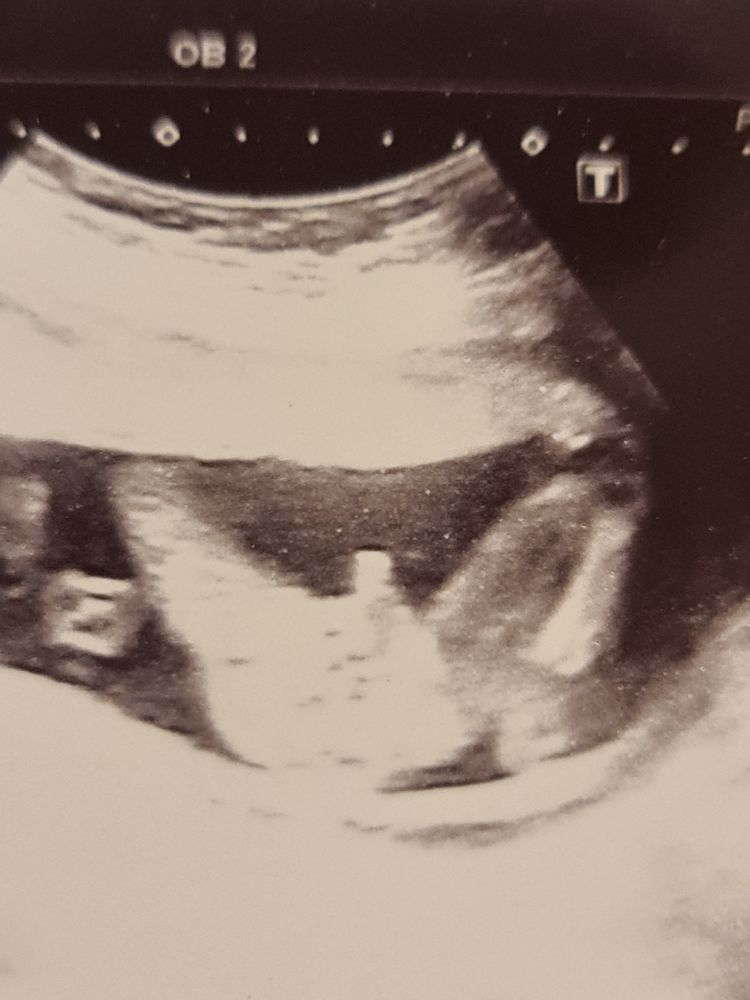

Татьяна, вы имеете ввиду отросточек сбоку (обвела) или то, что смотрит наверх? 🙃🙈 Изображение